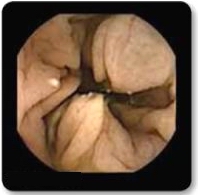

Pregătire corespunzătoare a tubului digestiv se aseamănă cu șofatul având parbrizul curat.

Pregătire necorespunzătoare a tubului digestiv poate împiedica vizualizarea totală a segmentului examinat sau poate duce la repetarea examinării după o pregătire suplimentară/corectă.